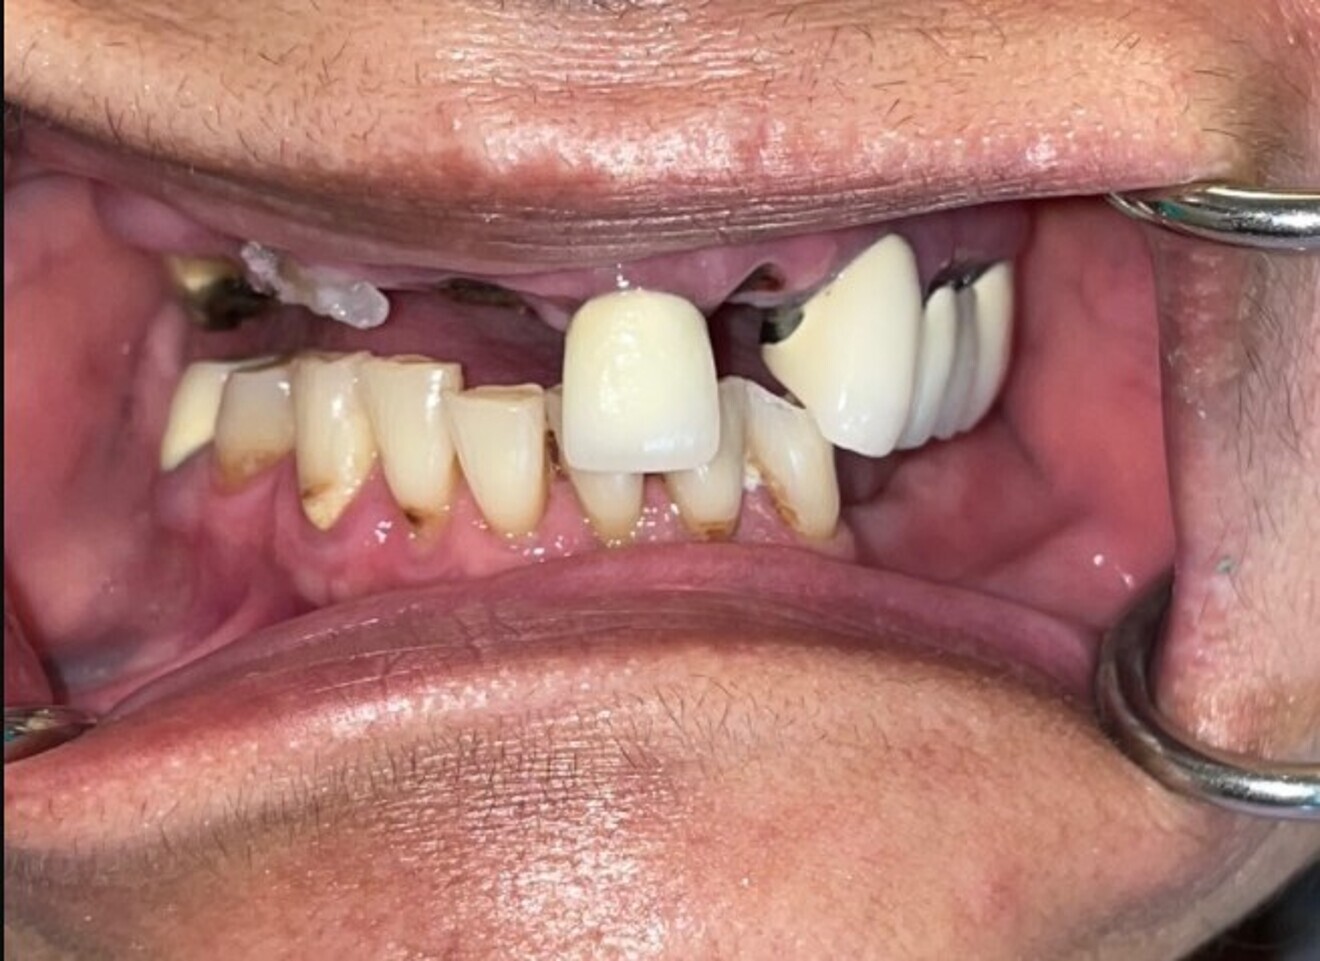

A 68-year-old female patient presented with failing dentition in the maxillary and mandibular arches due to years of neglect and patchwork dentistry. The patient was unhappy with the condition of her teeth and was embarrassed to go out in public. She had difficulty chewing owing to missing and fractured teeth in the maxillary arch, did not have any posterior mandibular teeth, and did not have a repeatable bite position. The patient had been to several dentists, who offered differing treatment plans, and was very confused regarding potential options to correct the deficiencies to improve her quality of life. Options that were presented included removable partial dentures, a maxillary complete denture and a mandibular removable partial denture, and implant-supported removable and fixed restorations for both arches. The patient wished to determine whether a fixed full-arch restoration could be considered for both the maxilla and mandible.

The patient presented with a collapsed bite due to missing, mobile and fractured teeth, which severely affected her ability to masticate food, resulting in embarrassment and a diminished quality of life (Fig. 10). After a thorough review of the diagnostic process, the treatment plan was presented and accepted by the patient for maxillary and mandibular implant-supported fixed restorations. At the request of the patient, one long procedure was scheduled to be completed under sedation administered by a dental anaesthesiologist. Once the patient had been sedated, bilateral mandibular blocks were accomplished with 2% lidocaine with 1:100,000 adrenaline and 4% articaine. The remaining mandibular teeth were extracted using periotomes, elvatomes, and forceps (all TBS Dental), and all the sockets were thoroughly debrided and then irrigated with 0.12% chlorhexidine gluconate (Fig. 11). Many of the extracted teeth were free of decay, root canal therapy or fillings, and therefore it was elected to utilise the patient’s own teeth to fabricate autologous grafting material for use in both maxillary and mandibular arches. The process of harvesting grafting material from tooth structure has been successfully reported in the literature and has become a great source of autologous tissue when teeth are to be extracted and grafting is required.

Fig. 10: Pre-op retracted view.